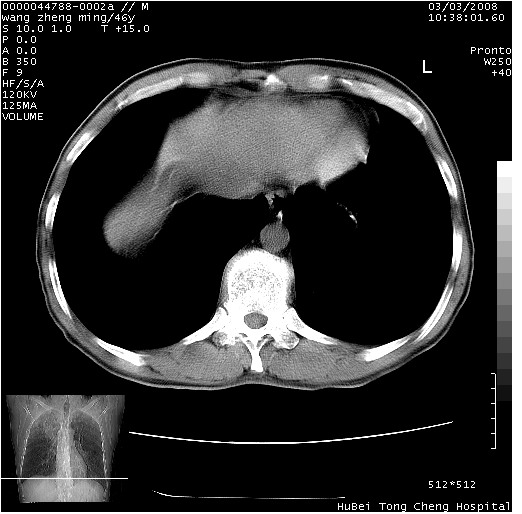

以下是引用卜一在2008-3-22 1:37:00的发言:[br]右肺实质性肿块,边缘不整,明显见毛刺征 分叶征及胸膜凹陷征,右上叶支气管明显变窄,远端散在的片状 斑片状实变影。另:左肺门较大肿块,支气管受累 变窄,远侧见阻塞性肺炎。纵隔内见肿大淋巴结。多考虑:右肺周围性肺癌伴左肺门 纵隔淋巴结转移!